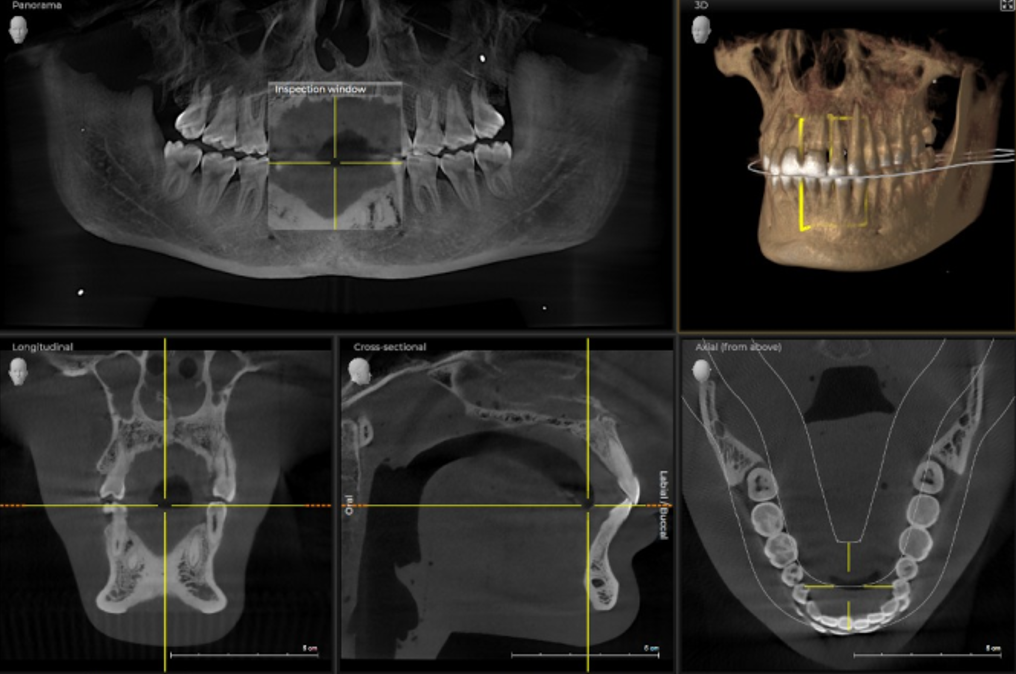

Дентальна комп’ютерна томографія (КТ) — це діагностична процедура в сучасній стоматології. Її результат дозволяє терапевту достовірно оцінити стан та анатомічні особливості кореневих каналів, локалізувати запальний процес. Ортопед може побачити точне розташування, будову СНЩС, імплантолог — оцінити параметри щелепної кістки, структуру, щільність та об’єм.

3D знімок — точний метод діагностики, лікар отримує повну інформацію про стан щелепно-лицьового апарату пацієнта, гайморових пазух. Отримані в результаті сканування знімки дають можливість стоматологу збільшувати, повертати і досліджувати під кутом області, що цікавлять, що неможливо при рентген-дослідженні. Також комп’ютерна томографія вимірює висоту, ширину кістки, визначає тип. Це потрібно, щоб підібрати розмір та тип імплантату при плануванні операції.

Ортопантомограма — це швидше допоміжний діагностичний інструмент, що надає оглядову картину і виявляє явну патологію. На відміну від панорамного знімка, 3D комп’ютерна томографія дає не одне плоске зображення щелепи. Лікар отримує низку послідовних зображень у різній проекції без спотворень, властивих панорамного знімка. Отримане тривимірне зображення дозволяє лікарю розглянути щелепно-лицьову зону на будь-якій глибині з усіх боків та кутів. Приклад: на панорамному знімку видно правильний імплант, а на КТ дослідженні виявлені помилки при встановленні.

ORTHOPHOS S 3D це прилад з всеохоплюючими можливостями. Починаючи з надчітких панорамних 2D знімків завдяки сучасному DCS сенсору і аж до максимальної гнучкості у виборі 3D обєму зйомки (11Х10, 8Х8, 5Х5). У коплексі з програмним забезпеченням SIDEXIS 4 відкриє нові можливості для Вашої практики.

Поле огляду 8 см х 8 см (VOL1) дозволяє відобразити всю щелепу пацієнта на одному знімку, що спрощує діагностику та планування лікування. При ендодонтичному лікуванні достатньо меншого обєму 5смХ5,5см (VOL2). Таким чином ми не тільки зменшуємо дозу опромінення а й скорочуємо час на постановку діагнозу. В режимі HD (висока роздільна здатність, 500 знімків зо один оборот ) при VOL2 з розміром вокселя 100 мкм Ви отримаєте надчіткі знімки для ендодонтичного лікування. Обєм 11 см Х 10 см надасть Вам максимум потрібної інформації.